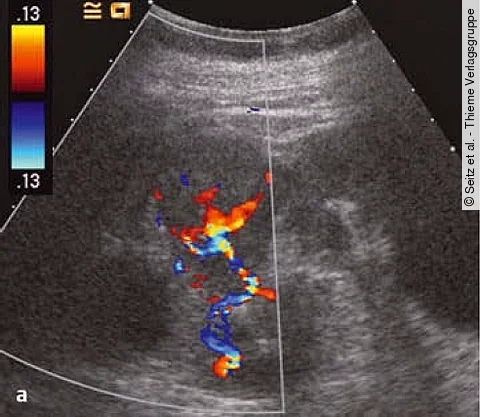

Multiple-Choice-Quiz: Auflösung: Wie schätzen Sie die Aussagekraft dieses Sonos ein?

Differenzialdiagnostisch kann es sich um Metastasen der bekannten früheren Karzinome handeln, auch ein Onkozytom ist zu erwägen. Gegen ein Nierenzellkarzinom spricht das Fehlen von Tumornekrosen.